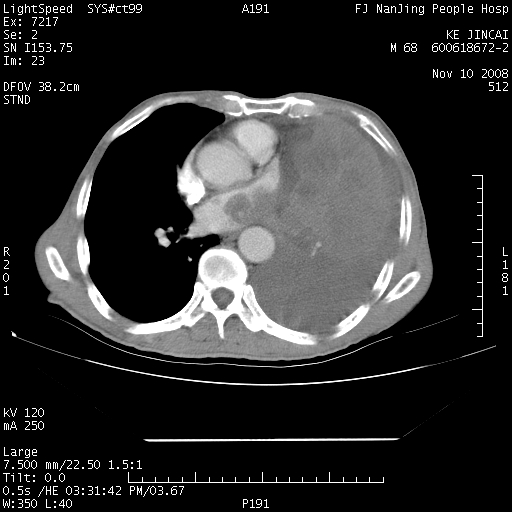

是个很有看头的病例,咋人气那么不旺?没多少人兴趣呢?这个病例几大怪:1   恶性肿瘤侵犯心肌左房怪,心肌一般不会被恶性肿瘤侵犯吧?2   左下肺均匀实变怪,内无含气,有别一般不张实变,含气肺泡完全为液体取代,而非一般不张实变的肺萎陷,冷不丁还以为是肿大的脾脏3   肿瘤本身怪,像tb肺不张4   这么有看头的病例没人气怪。呵呵。

左肺恶性肿瘤侵犯肺动脉,左心房内瘤栓,胸膜转移。